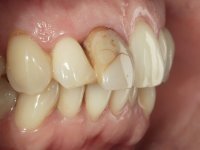

The treatment began with the placement of an intraradicular post and the creation of a new composite resin restoration. This procedure was performed with a surgical approach that allowed the remaining margins to be completely exposed, which were shown to be at a very infra-gingival level. Simultaneously, the periodontal pocket was curetted and root scaling and root planning of adjacent teeth were performed. Two months after this first intervention, the making of the crown began. A pre-print on silicone was performed to make a temporary crown with dual-cured composite resin. Gingival retraction was performed using the technique of kaolin paste compressed by the provisional crown. The impression was made using the double-mix technique with double viscosity with quick-setting silicone. In the laboratory, a crown with a ceramic-coated Zr infrastructure was made. The crown slightly overlapped tooth 12, allowing a dimensionally mimicry of the symmetrical tooth. Its fit was confirmed and approved by the patient; it was definitively cemented with resin-reinforced glass ionomer cement.